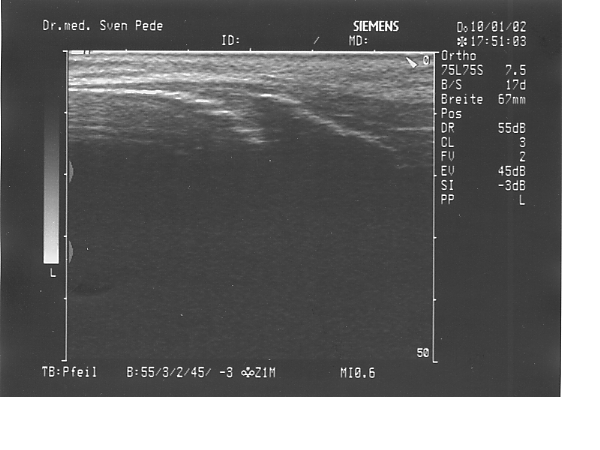

• SchlatterSONO1

• SchlatterSONO2